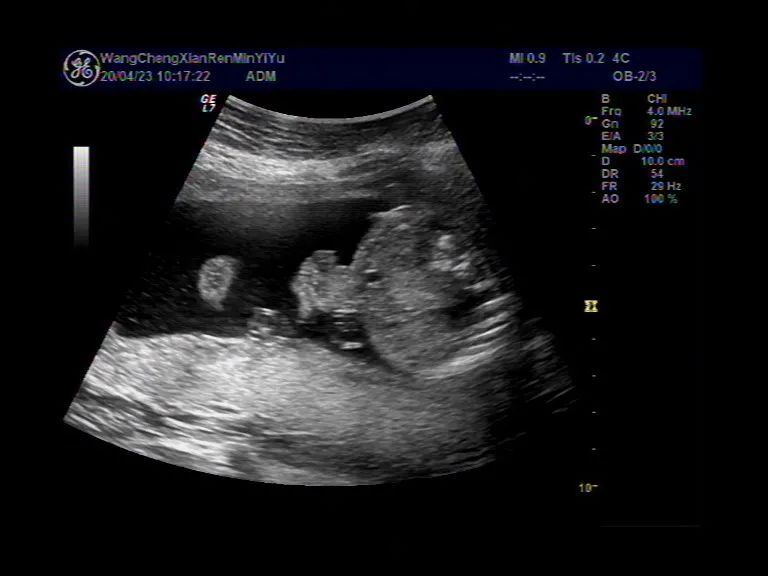

胎儿腹裂 - 超声医学讨论版 - 爱爱医医学论坛

图片尺寸1024x768